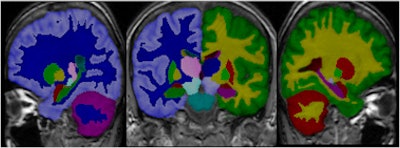

PredictAD aims to extract biomarkers from heterogeneous patient data and integrate them for objective and evidence-based diagnostics. For example its reasearch team is exploring how MRI can be used to measure atrophy in the mediotemporal lobe, which is recognized as a hallmark of Alzheimer's.

In current clinical practice, images are interpreted mostly only by visual inspection, but there is a need for objective measurements, according to Dr. Jyrki Lötjönen, the scientific coordinator of the project and principal scientist and adjunct professor of signal and image processing at the VTT Technical Research Centre in Tampere, Finland.

To meet this need, the PredictAD team has developed tools for measuring the size of the hippocampus, the atrophy rate of the hippocampus, and two approaches based on comparing patient data with previously diagnosed cases available in large databases. PET is also being studied in the project. A novel tracer developed recently especially for diagnostics of Alzheimer's disease provides promises for very early diagnosis of the disease.